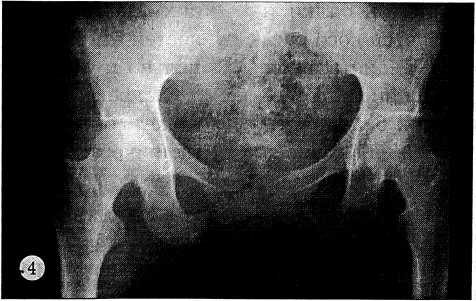

Рис. 4. Прямая обзорная переднезадняя рентгенограмма таза той же больной через 2 мес после операции: аппарат наружной фиксации снят, сохраняется правильная конфигурация тазового кольца в области поврежденных сочленений.

С тазового кольца аппарат снят через 2 мес (рис. 4), с голени — через 5 мес после операции. Двигательная активность восстановлена в полном объеме через 2 нед после снятия аппарата с голени. Пациентка осмотрена через месяц: жалоб нет, ходит без дополнительной опоры, походка правильная, безболезненная, в наблюдении не нуждается.